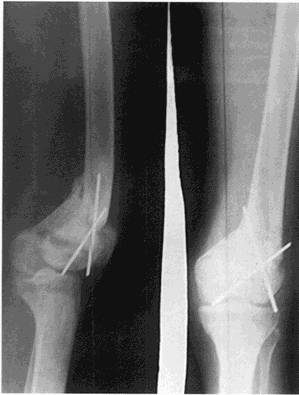

TÉCNICA QUIRÚRGICA

Con técnica de Aglieti, bajo anestesia peridural sobre mesa ortopédica e intensificador de imágenes, se realiza incisión lateral en muslo mediante la cual se separará el recto anterior del vasto externo. Se expone el tercio distal del fémur para realizar una V en el plano sagital comenzando por una marcación puntiforme con mecha delgada, iniciando por el vértice de la V, a dos traveces de dedo por encima del cóndilo externo.

Dichas perforaciones facilitan la sección final del hueso y nos dá una idea justo del plano a osteotomizar, esta se lleva a cabo por escoplo. Una vez obtenida la osteotomía total se corrige el valgismo varizando el cabo proximal, luego de verificar la correcta alineación deseada, se mantiene en posición con dos alambres de Kirschner entrecruzados.

Los extremos metálicos se seccionan al ras son cubiertos con partes blandas y cierre por planos. Luego inmovilización enyesada por 30 días inguinopedio, para al cabo de dicho período recortar transformándolo en calza por treinta días más.

Control radiográfico de rodilla izquierda post-quirúrgico el 18 de octubre de 1991